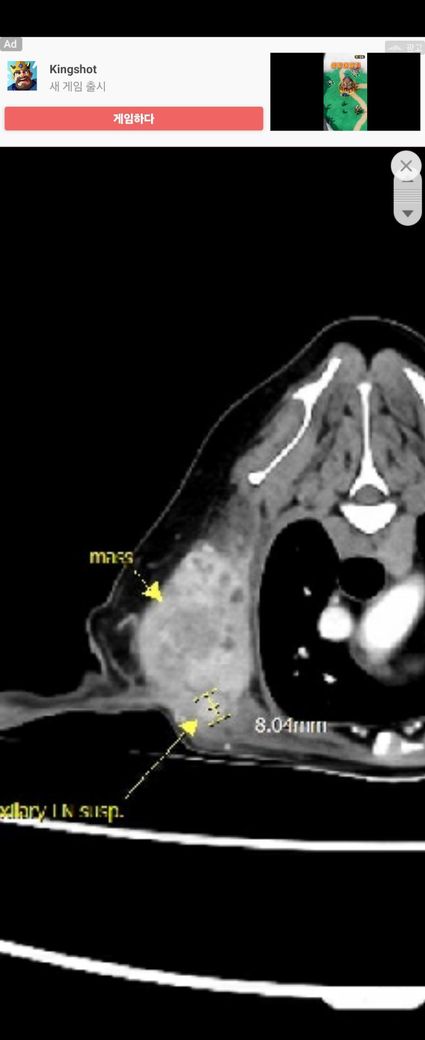

현상태에서는 CT 영상에서 조영전 영상의 HU값 비교를 통해 해당 종괴의 밀도가 지방밀도인지, 연부조직 밀도인지가 진단에 중요한 요소가 됩니다. 조영전 영상에서 HU값이 지방 밀도라면 조직검사 결과가 참으로 여겨지고, 연부조직 밀도라면 세침흡인검사 결과가 참일 가능성이 높아집니다. 하지만 조직검사 결과에서 침습성 지방종과 지방층염이 동반된 소견이라는 구절이 있기때문에 해당 상황에서는 HU값이 높게 즉, 연부조직 밀도라고 하더라도 침습성 지방종을 배제할 수 없게 됩니다.

다시 말해 첨부된 자료만으로는 어느 결과를 신뢰해야 하는지를 판단할 수 없으니 HU값의 측정이 가능한 원본 즉, DICOM file을 편집할 수 있는 주치의와 상의해 보시는걸 추천합니다.